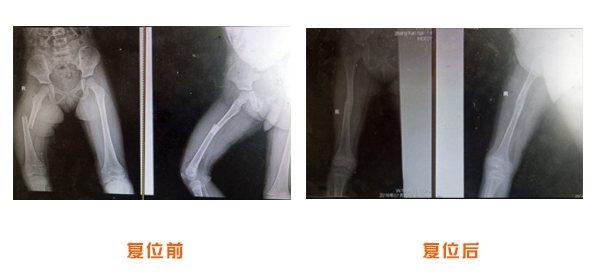

復位前后對比

尺橈骨骨折治療前后

尺橈骨克雷氏骨折治療前后